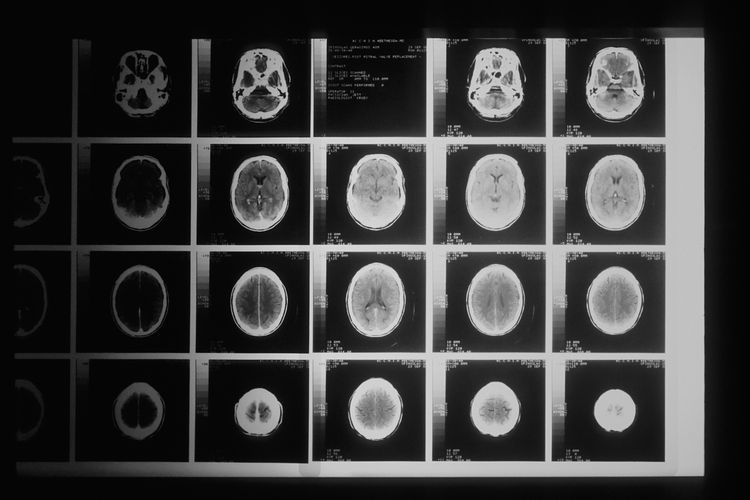

Врачи прошлого думали, что новорожденные дети практически нечувствительны к боли

«Раньше американские врачи делали операции на сердце младенцам без анестезии. К счастью, с этой практикой покончено. По крайней мере, её перестали использовать после 1980-х годов».